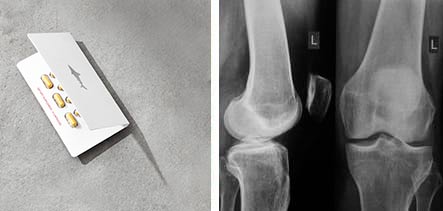

So habe ich von Shark Motion erfahren. Es ist ein Komplex aus Haifischknorpel, Collagen, Glucosamin, Chondroitin, Methylsulfonylmethan, Weihrauchpflanze, Nesseln, Teufelskralle Kurkuma- und Fingerkrautextrakt. Der Unterschied im Vergleich zu anderen Produkten ist, dass Shark Motion alle wichtigen Substanzen enthält, die notwendig sind für die Wiederherstellung der Gelenke. Was ich sehr mag an dieser Zusammensetzung, ist der Haifischknorpel. Ich habe gehört, dass dies einer der effektivsten Extrakte ist. Ich bat den Therapeuten, mir bei der Bestellung zu helfen. Er half mir dabei, Shark Motion mit einem Preisnachlass in Höhe von 50% zu erwerben, somit musste ich nur den halben Preis bezahlen. Was für ein Kleckerbetrag für die Gesundheit!

Die Sendung war nach 3 Tage da. Selbst die Verpackung spricht für ein hochwertiges Produkt. Mein erster Eindruck war sehr positiv. Nach ein paar Stunden ließ das steife Gefühl in Brust, Rücken und Nacken nach, der Schmerz war verschwunden.